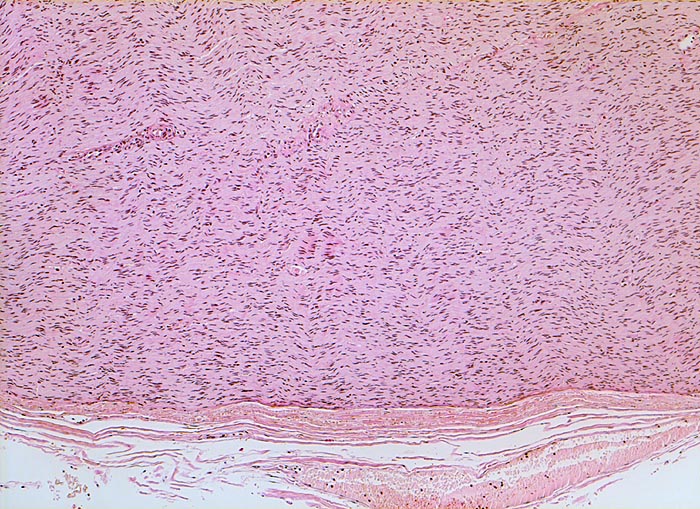

peripherer Nerv (Intercostalnerv)

Normalbefund

Nerv peripher

Schwannzellen mit langgezogenen Kernen in welliger Anordnung kennzeichnen den peripheren Nerven. Der Nerv ist umgeben vom Perineurium aus Bindegewebe und Gefässen.